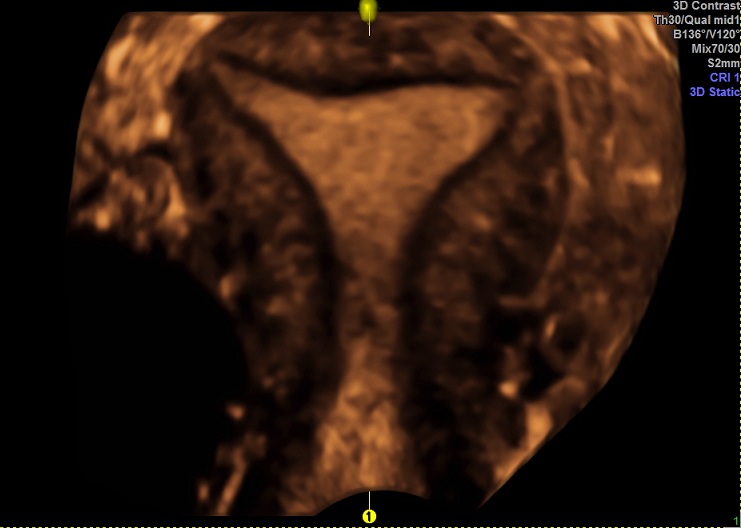

女性,24岁,原发性不孕1年余。

2015-3-10 月经第19天检查

内膜厚0.7cm

内膜血流:2级

内膜波动可见

左卵巢黄体 右卵巢囊性结构